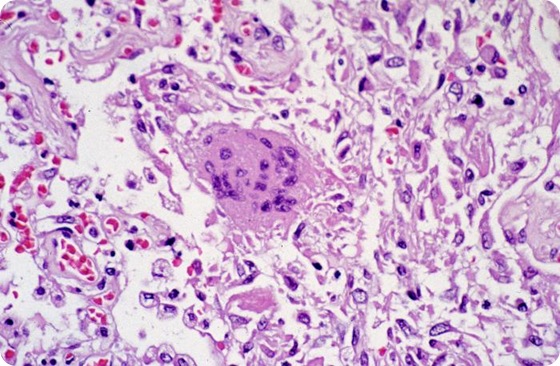

Researchers treated experimental mice with GRFT or a sham treatment and then inoculated them with the SARS virus. They analyzed the antiviral activity of GRFT and the extent to which the virus was able to invade and replicate in the mice at two, four and 10 days after infection. They found that mice who had not been treated with GRFT showed 20 times more plaque-forming units of virus than treated mice. They also noted that the lungs of untreated infected mice showed extensive necrotizing bronchitis and prominent edema, while mice treated with GRFT showed evidence of significantly less severe lung damage. Additionally, mice treated with GRFT did not experience the drastic weight loss of untreated mice, which lost 35 percent of their body mass.